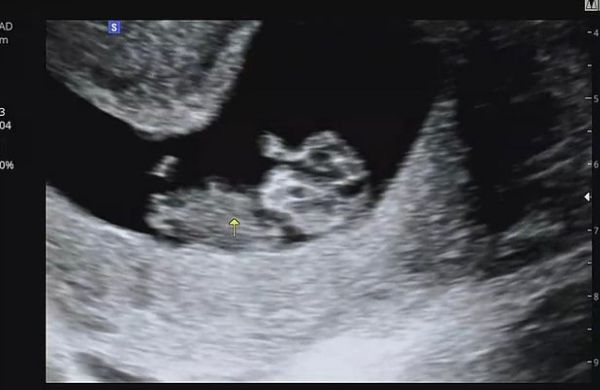

/사진=최희 인스타그램 캡처